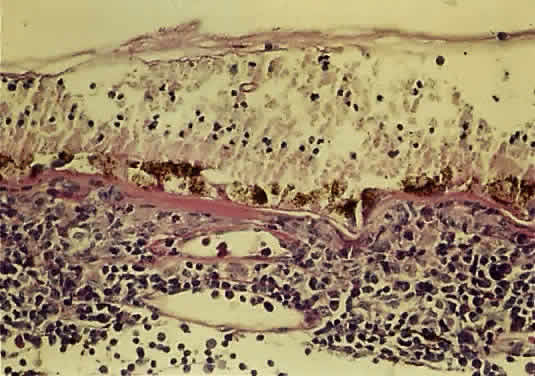

The histopathology of ARN shows profound necrosis of the retina, retinal arteritis, and viral inclusions in retinal cells.1 Examination of an eye with end-stage ARN secondary to VZV revealed diffuse full-thickness, necrotizing retinitis, replacement of sensory retinal structures by glial tissue, occlusive retinal arteritis, granulomatous choroiditis, optic neuritis with ischemic optic atrophy, and VZV in the choroid and the choriocapillaris55 (Fig. 15).

|